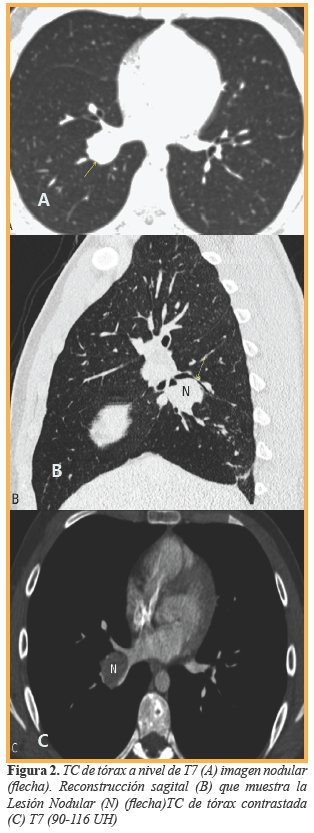

Al cabo de 4 semanas, en el seguimiento clínico-radiológico, los padres refieren accesos de tos a predominio nocturno que cede con el broncodilatador, pero se observó una imagen nodular en proyección del cuerno inferior del hilio derecho que medía 23x25x25 mm en sus diámetros (anteroposterior, transversal, longitudinal), la cual no se visualizaba debido al proceso de condensación en la fase neumónica (Figura 1). Se decidió realizar Tomografía Computarizada (TC) de tórax a nivel de T-7 Ventana de pulmón (A) para su caracterización la que constató que hacia la luz del bronquio para el lóbulo inferior derecho crecía una lesión nodular tumoral de 29x24x25 mm (Anteroposterior, Transversal, longitudinal) con densidad de 40 UH (Unidades Hounsfield) la cual oblitera parcialmente la luz del bronquio en el estudio simple (Figura 2) y 90-116 UH en el estudio contrastado (C) mostrando lesión nodular que capta intensamente el contraste (Figura 2). En el postprocesamiento, se obtuvo broncoscopía virtual la cual validó la presencia de una lesión endoluminal nacarada que obstruye parcialmente la luz del bronquio para el lóbulo inferior derecho (Figura 3) adyacente a la misma, se observa la emergencia del bronquio para el lóbulo medio.